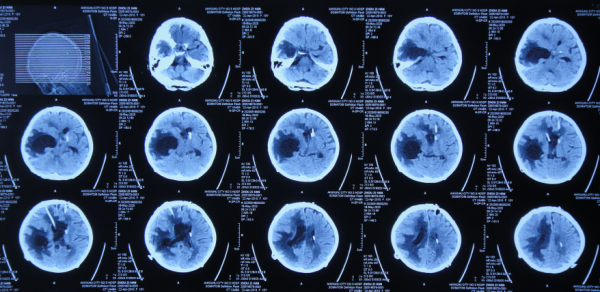

在第2家醫院治療16天即2019年12月27日,按計劃術前查頭部CT(圖-14)後進行了顱內腫瘤切除術。

圖-14:2019年12月27日頭部CT

在第2家醫院治療18天即2019年12月29日(顱內腫瘤切除術後2天),查頭部CT示腦積水,顱內腫瘤切除術後,留置引流管(圖-15)。

圖-15:2019年12月29日頭部CT

在第2家醫院治療19天即2019年12月30日,進行了右側顱內壓感測器腦室內植入+腦室外引流術(圖-16)。

圖-16:2019年12月30日頭部CT

因右側顳角仍大,次日做了右側腦室外引流管調整術(圖-17)。

圖-17:2019年12月31日頭部CT

在第2家醫院治療31天即2020年1月11日(顱內腫瘤切除術後16天),查頭顱CT示腦室再次擴張(圖-18)。

圖-18:2020年1月11日頭部CT

在第2家醫院治療36天即2020年1月16日(顱內腫瘤切除術後21天),按計劃明天進行腦室腹腔分流術,術前查頭部MRI示腦室擴張(圖-19)。

圖-19:2020年1月16日頭部CT

在第2家醫院治療37天即2020年1月17日(顱內腫瘤切除術後22天),進行了雙側腦室腹腔分流術(圖-20)。

圖-20:2020年1月17日頭部CT

但腦室腹腔分流術後8天時間內,三次複查頭部CT示腦室又逐漸增大(圖-21、圖-22、圖-23),給予調壓處理。

圖-21:2020年1月20日頭部CT

圖-22:2020年1月23日頭部CT

圖-23:2020年1月25日頭部CT